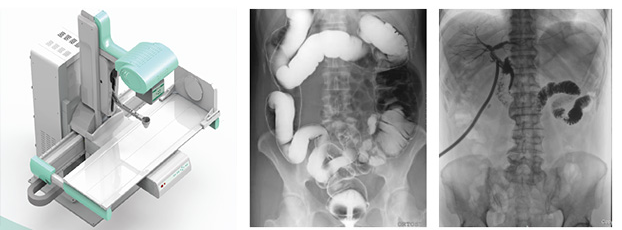

随着现代医疗技术快速发展,传统的X射线技术实现数字化,出现了多功能DR。多功能DR采用数字影像平板探测器取代传统胶片,直接捕获X线影像,并转化为高清晰数字图像,对比传统的间接影像设备,多功能DR可以直接将X射线转化成图像,成像更清晰,放射剂量更小。

多功能DR大大提高了普通放射设备准确诊断的能力,为临床创造了价值,它可以进行全身各部位的拍片、透视和点片摄影。接下来小编给大家介绍一下这三种模式的区别。

拍片摄影是利用X线穿过人体被检查部位并感光在胶片上形成影像而进行诊断的方法,它有胶片可供长时间观看分析,便于诊断分析及会诊读片、资料存储。另外,由于曝光时间很短,人体受到的辐射比透视小得多。但是当某处有疑点时无法转动体位从不同角度观察,无法看全貌。

透视是用X线穿过人体被检查部位在荧光屏上显示的影像而进行诊断的方法,连续出射线(摄影),在检查时可以转动病人的身体,从各种不同的位置和角度来观察病变的状况,也可以观察器官的运动功能,能够立即得到检查结果,进行介入性的操作等。但是因为透视会持续输出射线,病人接受的辐射剂量较大,并且透视对细微病变和厚实部位观察不太清楚,不能留下长久性的记录。

点片摄影是在透视的条件下,对病变部位进行可视化观察,待发现疑似病变部位的时候进行瞬间点片,从而能够准确获取病变部位的高清影像用于临床诊断,从而在一定程度上降低漏诊误诊率。病人不动,通过选择键由透视直接切换摄影的曝光过程。在透视过程中,保存一幅静止的图像。常用于消化道、胆系造影下的摄影等。它既可以观察运动器官的运动功能,又能在有感兴趣的图像时,对胶片曝光保留感兴趣的图像,便于进一步诊断。